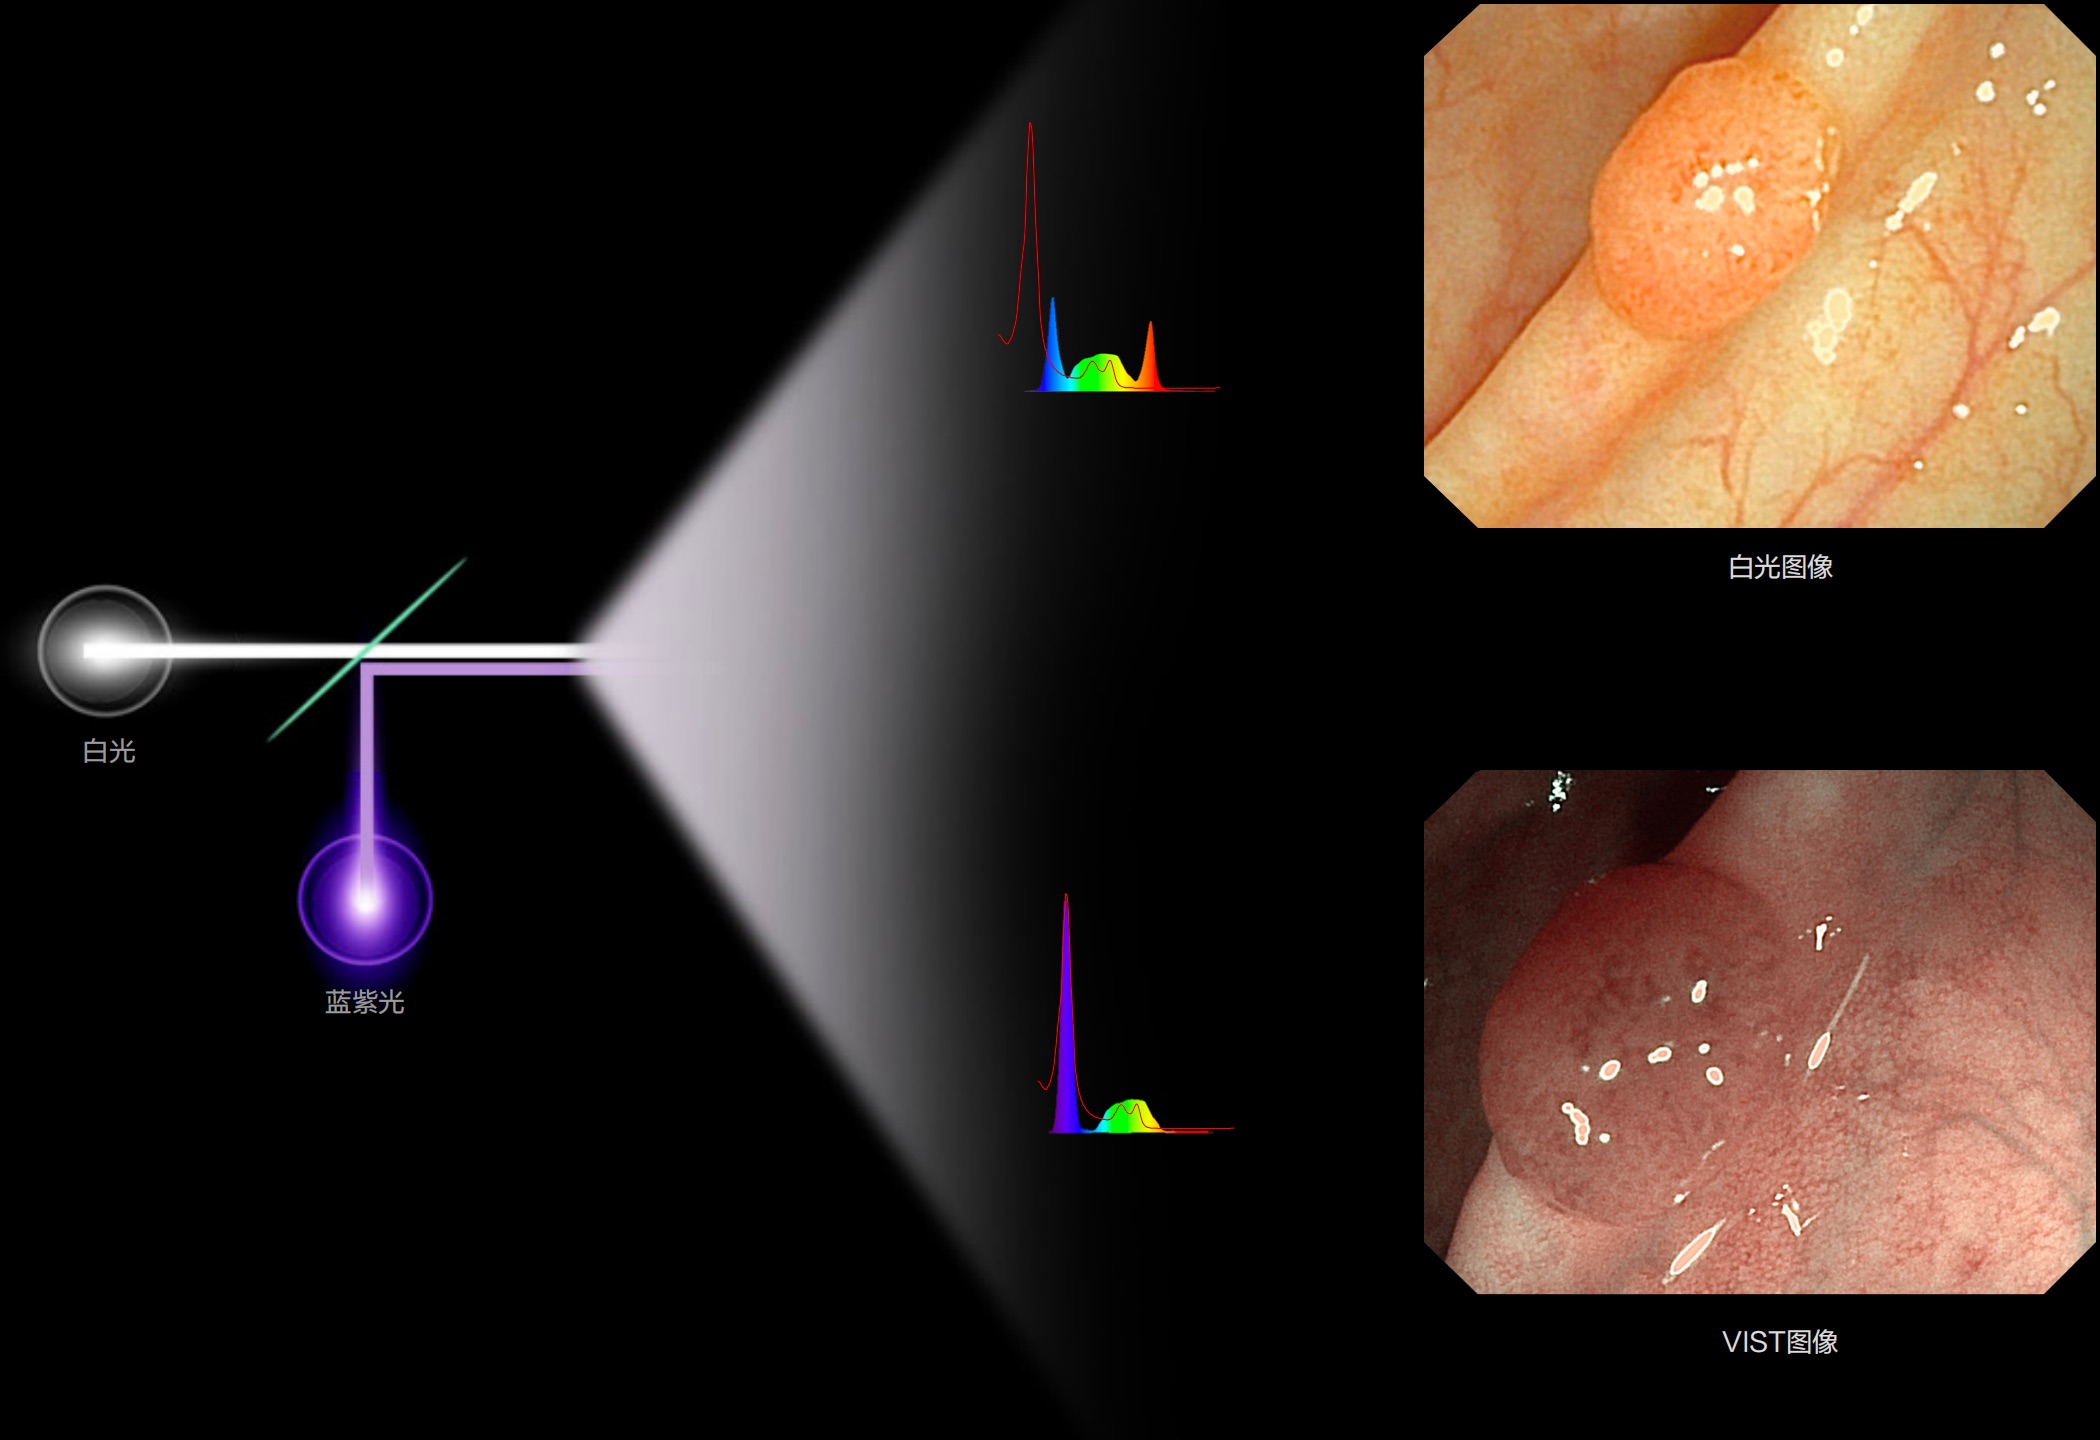

照明光谱

光谱提取

光谱提取能量汇聚

RGB图像重建

染色模式显示

白光图像

SFI图像

(Versatile Intelligent Staining Technology)

能够凸显黏膜浅层血管轮廓和黏膜表面微结构,适用于中、近景观察下的早癌精确诊断。